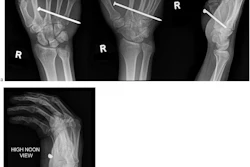

The study assessed data from emergency x-ray use of the BoneView AI tool at Bærum Hospital in Gjettum, comparing findings by AI-assisted radiographers and AI alone to assess both the accuracy of the AI and the subsequent effect its findings had on patient management. The study included data from 1,052 AI-assisted x-ray exams taken in January 2024.

Brurberg and colleagues also found that 18% of AI’s false positives and 50% of its false negatives were for knee and lower leg x-rays, despite these exams constituting only 12% of the total. Most of the false-positive findings (73%) were due to incorrect recognition of fractures, they noted, but 21 false-positive findings were identified as bone lesions (15) and dislocations (5), and there was one false-positive effusion finding.

While false negatives were rare apart from the knee and lower leg findings, one finger fracture requiring treatment was missed by AI, the authors wrote, deeming it the only false negative by AI to have potentially resulted in delayed treatment and clinical consequences.